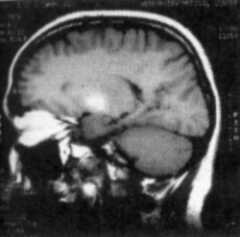

I would like to mention some chapters which I found of special interest. In the chapter on clinical neurotoxicology, we are told that several toxins can actually be diagnosed by CT and MRI. There is even a table which tells us of the various toxins which can be detected by these methods. There are pictures showing MRI scans of brain showing deposition of manganese in the basal ganglia area. These areas are seen as bright oval areas. Other poisons which can thus be detected (i.e. either by CT or MRI or both) are methanol (putamen and globus pallidus lesions), toluene (loss of differentiation of gray and white matter, cerebral and cerebellar atrophy and a host of other changes), Hydrogen Peroxide (Ischemic changes and cerebral infarction), organic solvents (cerebral atrophy) and Carbon Monoxide (basal ganglia lesions, particularly globus pallidus and white matter lesions).